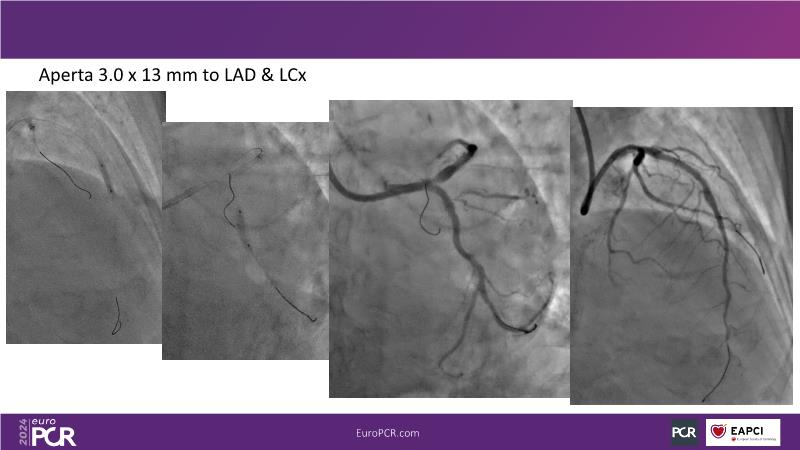

From innovation to reality: the impact of Cre8 EVO technology on complex PCI

Sponsored by Alvimedica